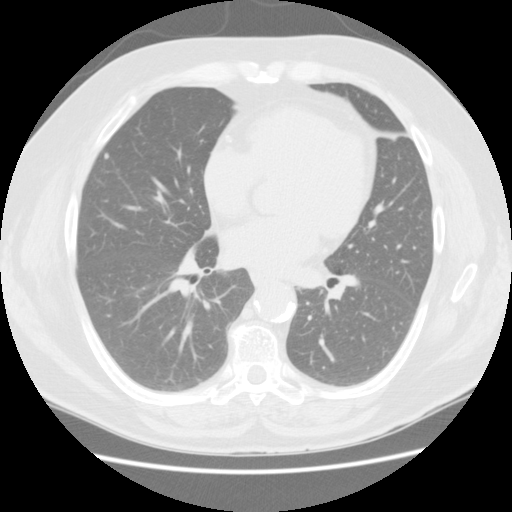

【EIRL Chest CTによる表示例】

① 標準線量CT